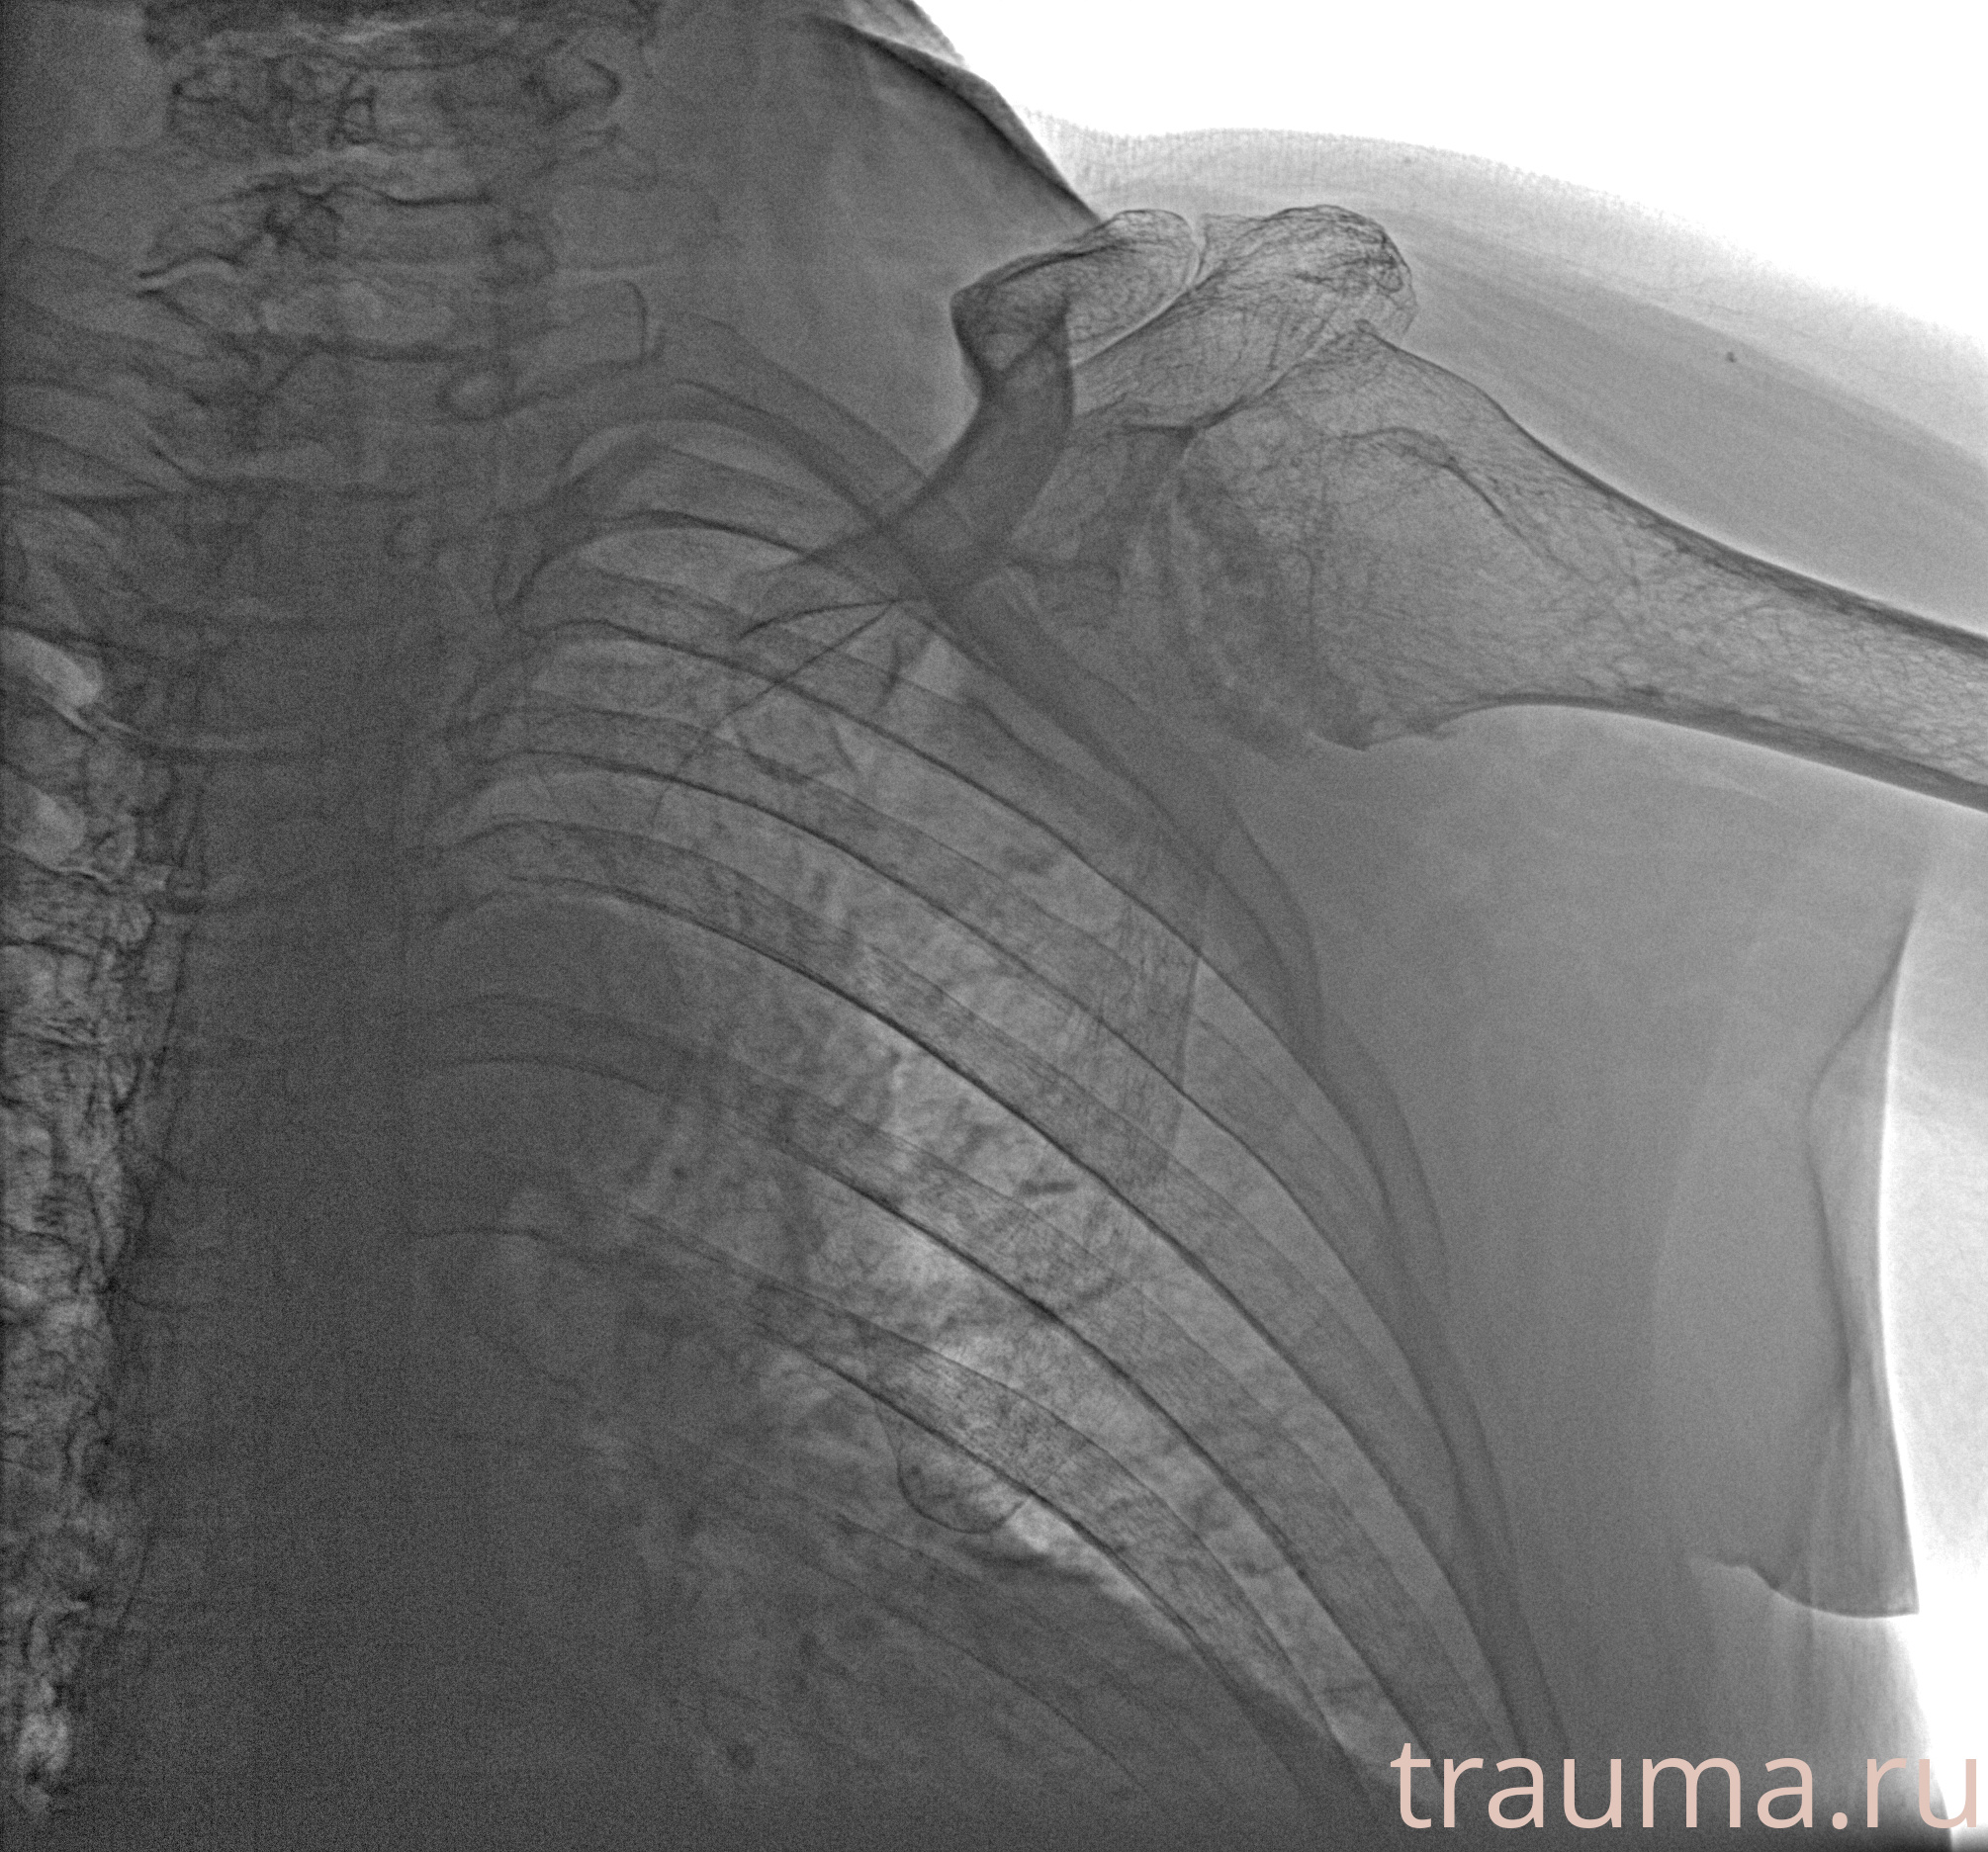

Рентгенограммы

Рентген на дому: по вашему адресу приезжает врач-рентгенолог, травматолог-ортопед с мобильным рентгеновским аппаратом, проводит диагностику травмы или заболевания, делает необходимые рентгенограммы, дает рекомендации по дальнейшему лечению. Получить качественные снимки в домашних условиях возможно благодаря уникальной методике, разработанной МосРентген Центром для института  Склифосовского